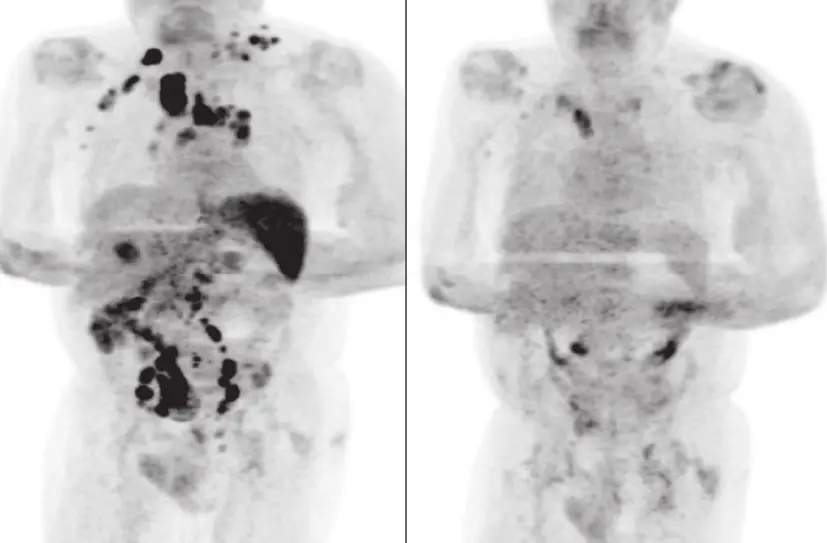

Legenda: Tomografia computadorizada mostra redução do linfoma após paciente ser infectado pelo coronavírus (imagem do lado direito)

Foto: Reprodução/Britsh Journal of Haematology

Um homem de 61 anos com linfoma de hodgkin, câncer no sistema linfático, teve remissão da doença após ser infectado pelo novo coronavírus. O caso foi publicado pelo Britsh Journal of Haematology, periódico médico do Reino Unido, em 2 de janeiro.

O homem passou 11 dias internado e recebeu alta para se recuperar em casa. Quatro meses depois, a avaliação médica indicou que o linfoma havia reduzido e exames revelaram resolução generalizada da linfadenopatia.